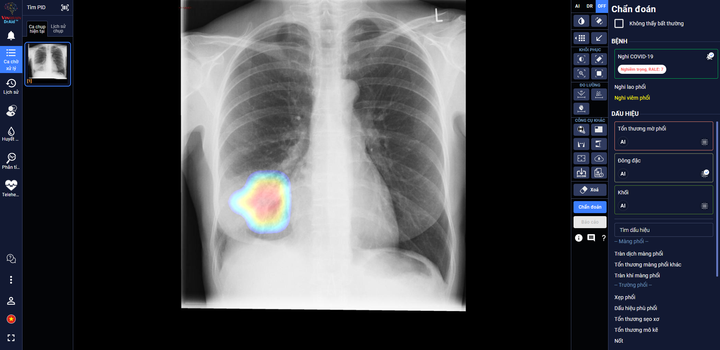

DrAid giúp bác sĩ theo dõi mức độ tổn thương phổi ở một bệnh nhân F0 trên ảnh X-quang phổi.

Trong các bệnh viện thu dung điều trị COVID-19, DrAid cho COVID-19 giúp các bác sĩ đánh giá mức độ tổn thương phổi của bệnh nhân COVID-19 qua các ngày, từ đó đưa ra các chỉ định điều trị kịp thời và hiệu quả cho bệnh nhân.